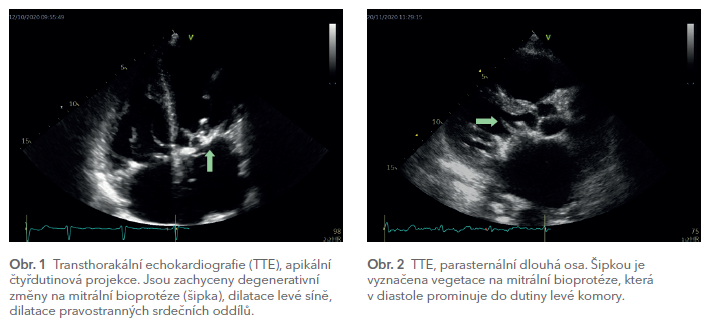

Transthorakální echokardiografické vyšetření (TTE) ukázalo degenerativní změny na mitrální bioprotéze se ztluštěním, kalcifikacemi a omezením hybnosti jejích cípů, s doprovodnou kombinovanou vadou se středně významnou stenózou a lehkou regurgitací (plocha ústí MVA při arytmii 1,06–1,32 cm2). Systolická funkce levé komory byla mírně snížena (ejekční frakce, EF 45–50 %). Levá síň byla výrazně dilatovaná. Byla přítomna i dilatace pravostranných srdečních oddílů s významně sníženou systolickou funkcí pravé komory (obr. 1).